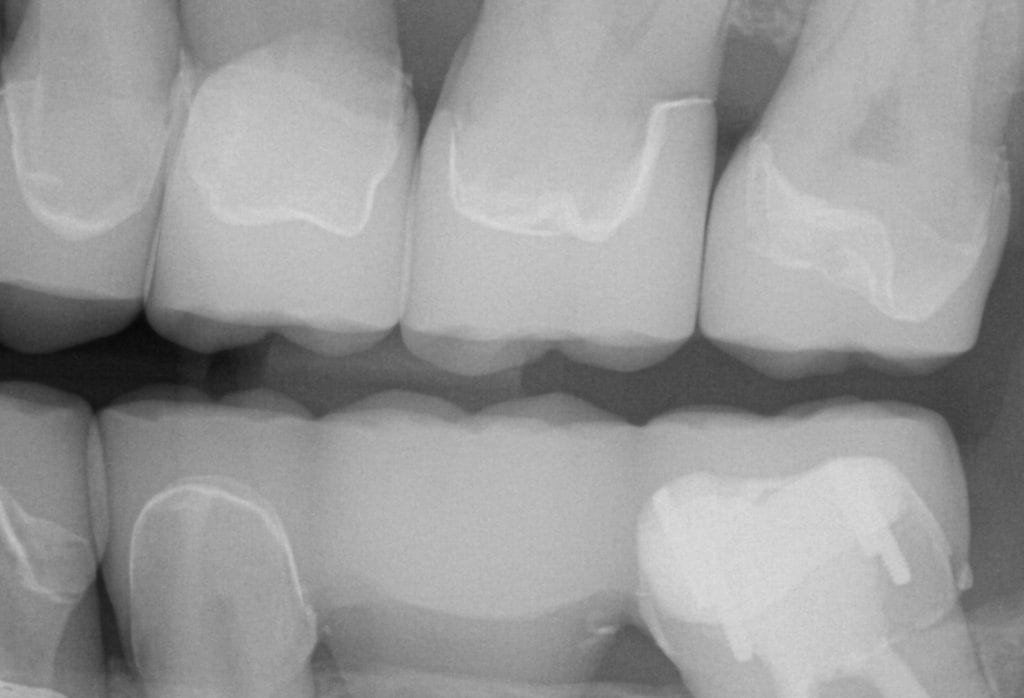

ONE WEEK POST-OP RADIOGRAPHS / CEMENT CHECK